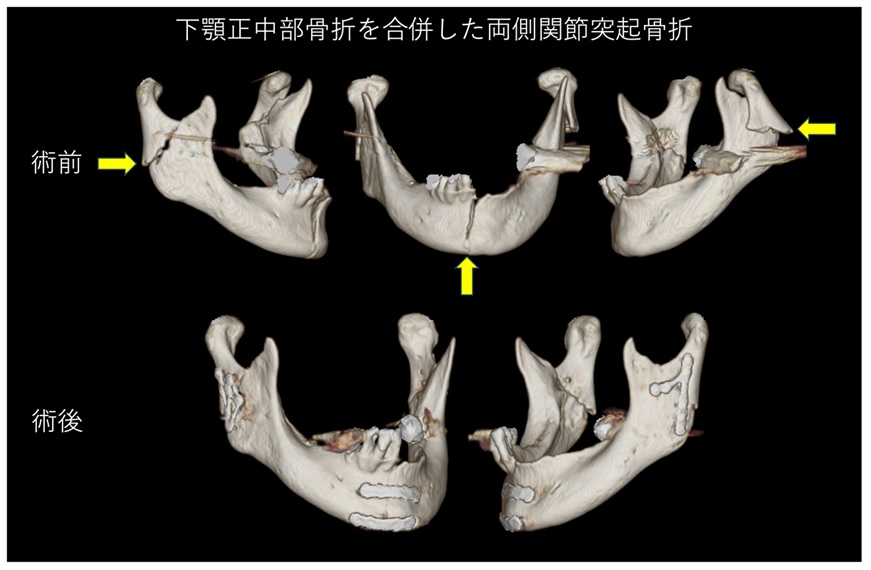

顎顔面外傷

顎顔面外傷は、顔面や顎の骨や歯、軟組織に損傷をもたらす怪我です。交通事故、スポーツの怪我、転倒、暴力などが主な原因となります。

症状には、顔の腫れ、痛み、出血、視覚障害、噛み合わせの異常、顎の動きの制限などがあります。

X線検査で正確な診断を行い、骨折の有無や損傷の程度を確認します。

軽度の骨折の場合では、骨が自然に治癒するのを助けるために、ワイヤーやエラスティックバンドを用いて上下の歯を固定する顎間固定が行われます。

通常、4~6週間の固定期間が必要です。重度の骨折や複雑な骨折の場合は、手術が必要です。

手術では、骨を正しい位置に戻し、プレートやスクリューを用いて固定します。手術は全身麻酔下で行われ、術後は数日の入院が必要です。

治療後は、顎の機能回復を促進するためのリハビリテーションが行われます。口を開ける練習や、柔らかい食事から固い食事へと段階的に移行していきます。顎の動きを正常に戻し、日常生活への早期復帰を目指します。